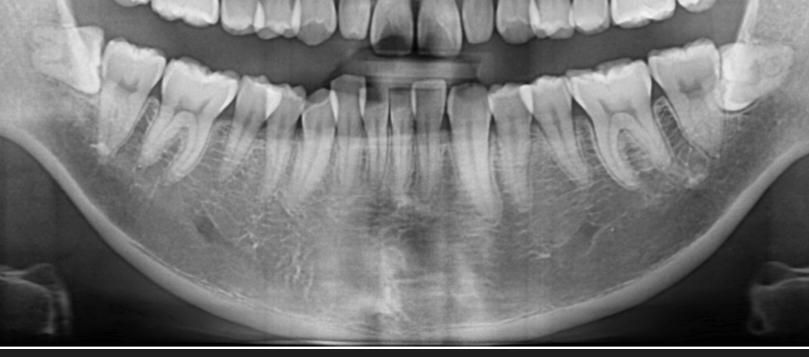

사랑니 발치하려는데 발치 난이도, 통증정도(지속시간)

, 발치시간, 비용 등 대략적으로 궁금해서 알려주시면 감사하겠습니다.

옆으로 누어있는 수평매복 사랑니 입니다. 이런 사랑니는 치아를 절단하여 뽑게 되니 간단한 수술에 해당합니다. 발치후 통증이 3-4일 정도 지속됩니다. 수술에 걸리는 시간은 1시간 정도? 비용은 의료보험 적용됩니다.

매복사랑니라 잇몸도 절개를 하고 치아도 절개를 해야될것같습니다. 비용은 의료보험이 적용되기 때문에 크게 부담은 되지 않지만 지혈제는 비보험이라 치과마다 다를수 있습니다. 시간은 30분정도 생각하셔야될것같습니다.

발치난이도: 중상정도입니다

통증은 미약하게라도 1주일 지속되기도 합니다

시간은 30분 ~ 1시간 내외입니다

비용은 지혈제 포함해서 7~8만원 내외입니다